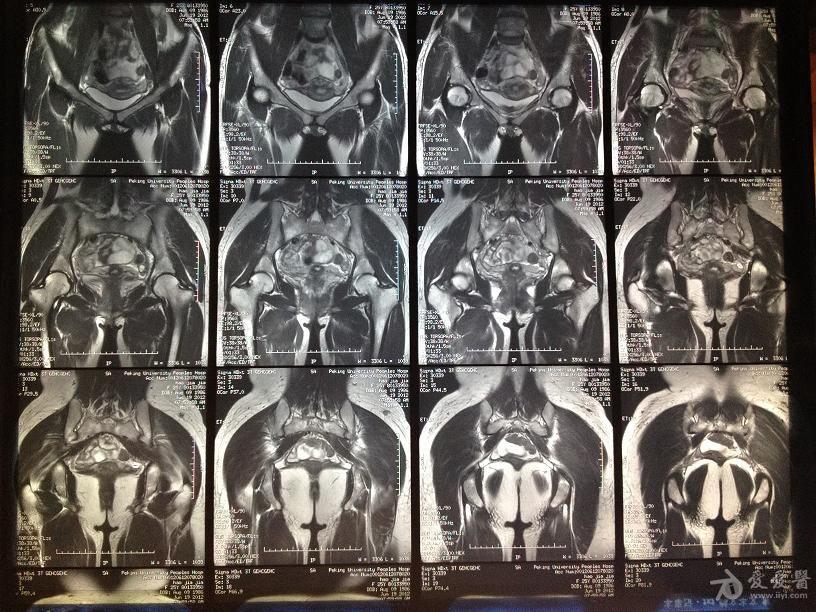

正常髋关节核磁图片

正常髋关节核磁图片,髋骨图片构造图解

髋关节核磁图片

髋关节核磁共振